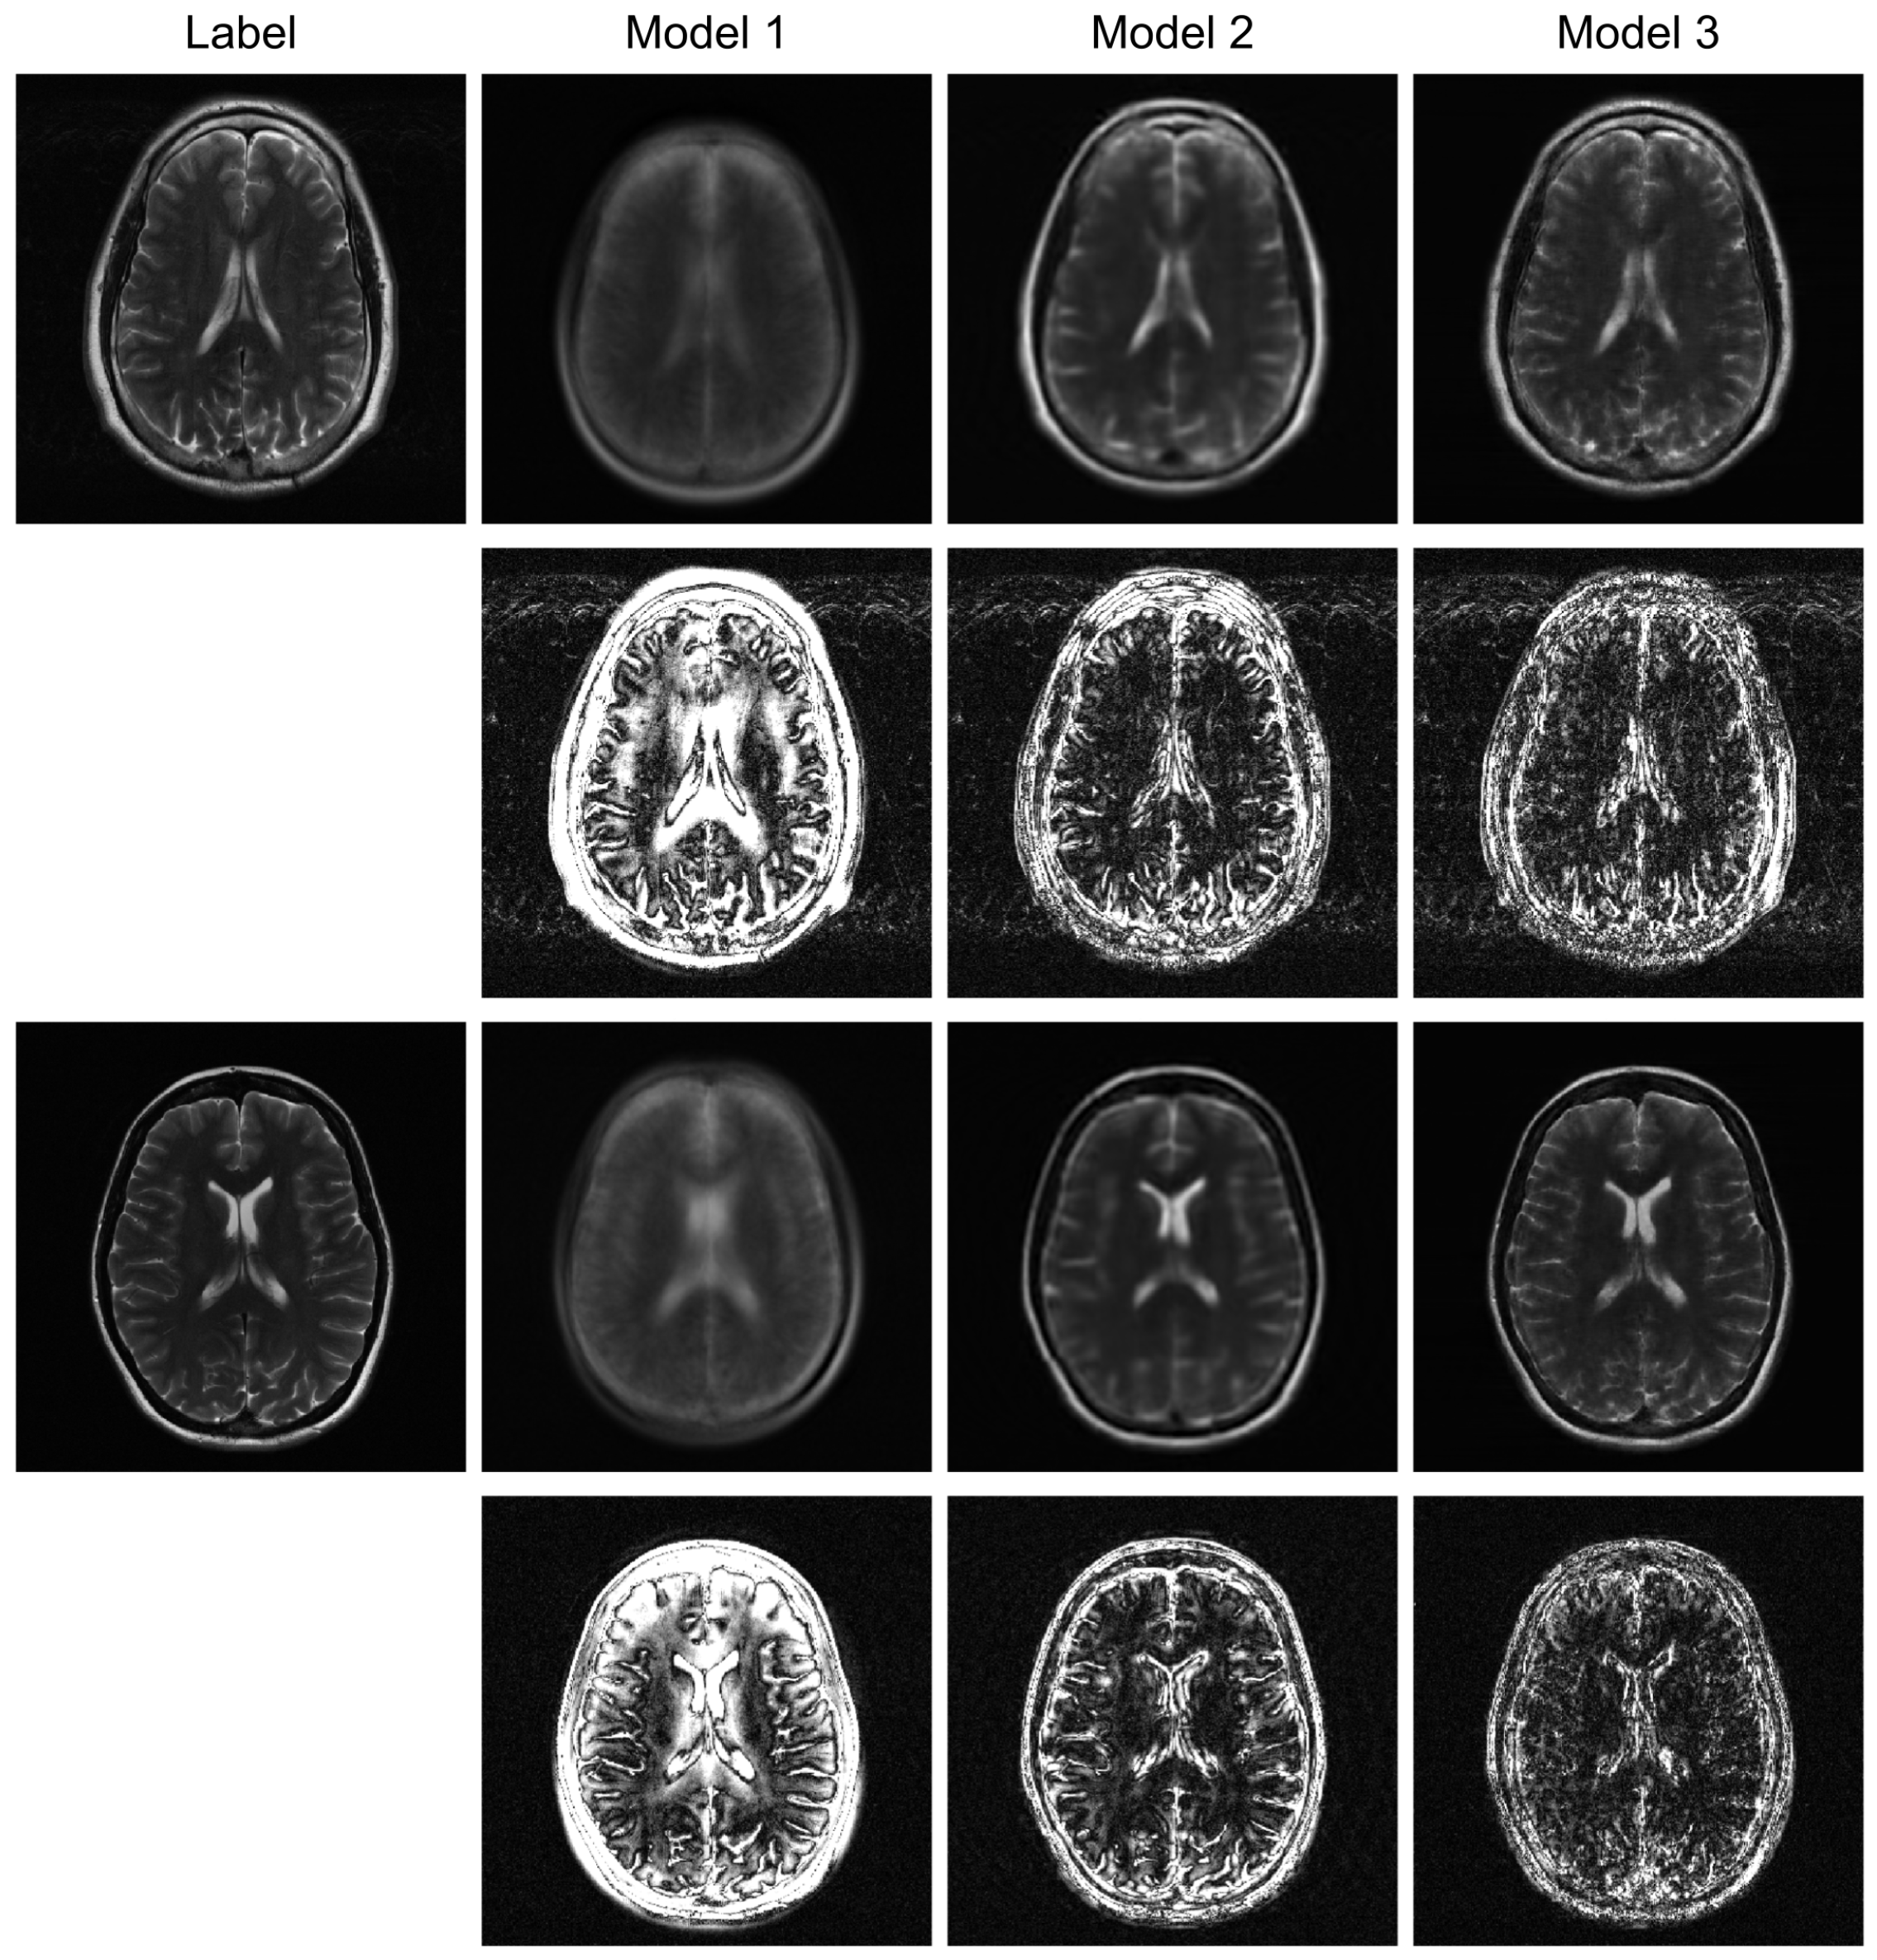

To further evaluate the robustness of our proposed model, we conducted additional experiments under higher acceleration factors (R = 8) and with different undersampling patterns (regular and random). For the random sampling scenarios, a new undersampling mask was randomly generated for each sample, which prevents the model from overfitting to a fixed pattern and enhances generalization. The qualitative results are presented in Figure 3, Figure 4 and Figure 5, and the corresponding quantitative analysis is summarized in Table 1. At a higher acceleration factor of R = 8 (Figure 4 and Figure 5), the performance gap between the models becomes more pronounced. While all models exhibit increased artifacts compared to R = 4, Model 3 consistently preserves anatomical structures more effectively than the other models, particularly in the more challenging random sampling scenario (Figure 5). The quantitative results in Table 1 align with the visual assessment. Across all tested scenarios—R4 random, R8 regular, and R8 random—Model 3 consistently achieves the lowest nMSE and the highest SSIM and VIF scores.

The comparison between Model 2 and Model 3 effectively serves as an ablation study, isolating the contribution of the BiRNN module. The significant performance improvement observed in Model 3, particularly under high acceleration (R = 8) and random sampling conditions (Table 2), underscores the critical role of processing k-space data directly. While the Transformer decoder in Model 2 can reconstruct global structures from the encoder’s latent features, it struggles with the complex, non-local aliasing artifacts inherent in undersampled data. The BiRNN module in Model 3 addresses this by interpreting k-space as sequential data, effectively capturing the structured correlations along the phase-encoding directions. This allows the model to disentangle aliasing patterns from true anatomical features before the final fusion step, resulting in superior artifact suppression and detail preservation, as visually confirmed in Figure 4 and Figure 5.

Figure 5. High-acceleration (R = 8) reconstruction with a regular sampling mask. The visual results and corresponding error maps (10× amplification) illustrate each model’s effectiveness in handling coherent aliasing.